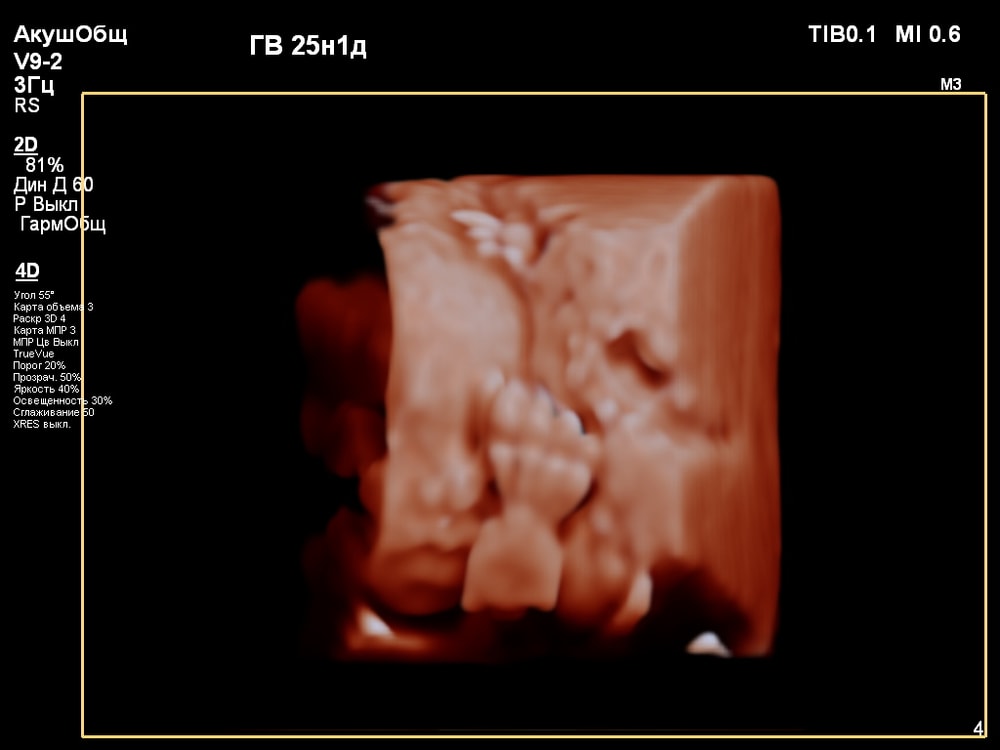

3D/4D УЗИ в 25 недель

УЗИ, КТГ, доплерПервая фотосессия малыша ещё в животике!😍 СНИМКИ С УЗИ👇

Когда переключили на 4D режим было сначала непонятно, что изображено на экране. Но врач всё показывала и обьясняла что на нём: где носик, губки, подбородок, что у личика ручки, малыш что-то жуёт, губками шевелит. Тогда картина начала вырисовываться и всё стало понятно, и в движении тоже)).

За 30 мин удалось увидеть многое (ребёночек не спал)! Он у меня в принципе парень активный, особенно лёжа на спине): на УЗИ, ещё в самом начале, малыш показал указательный палец и почесал им нос 😂, потом пытался большой палец засунуть в рот и пососать. Забавно было, когда он начал зевать и прикрывать ротик ладонью (воспитанный растёт). Ну и конечно, на радость родителям малыш улыбался🥰. Александра Евгеньевна смогла поймать все эти моменты и запечатлеть на снимке). Когда ребёночек закрывался, отворачивался - врач проводила общее 2D исследование, потом возвращалась к 4D.

😁😍🥹Я ИСПЫТАЛА НЕВЕРОЯТНУЮ РАДОСТЬ, ВОСТОРГ И УМИЛЕНИЕ)): впервые увидеть не абстрактные черно-белые тени, а узнаваемое личико своего ребенка, его движения – это мощнейший эмоциональный опыт, укрепляющий связь с малышом еще до рождения! Увидеть, как малыш активно двигается, зевает, сосет пальчик, улыбается – вызывает бурю положительных эмоций.